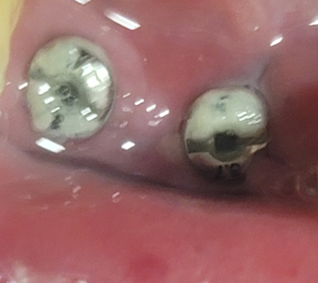

위의 사진에서 x표시 있는 2개의 치아를 1차 수술에서 발치하고 바로 임플란트식립+인공뼈 추가하고, 힐링 어버트먼트까지 부착을 하였습니다. 1차 수술 당시에는 힐링어버트먼트가 잇몸으로 많이 가려진 상태였습니다.

• 1번 째 사진

• 2번 째 사진